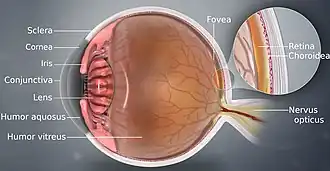

The eye can be considered as a living optical device. It is approximately spherical in shape, with its outer layers, such as the outermost, white part of the eye (the sclera) and one of its inner layers (the pigmented choroid) keeping the eye essentially light tight except on the eye's optic axis. In order, along the optic axis, the optical components consist of a first lens (the cornea—the clear part of the eye) that accounts for most of the optical power of the eye and accomplishes most of the focusing of light from the outside world; then an aperture (the pupil) in a diaphragm (the iris—the coloured part of the eye) that controls the amount of light entering the interior of the eye; then another lens (the crystalline lens) that accomplishes the remaining focusing of light into images; and finally a light-sensitive part of the eye (the retina), where the images fall and are processed. The retina makes a connection to the brain via the optic nerve. The remaining components of the eye keep it in its required shape, nourish and maintain it, and protect it.

The eye is not shaped like a perfect sphere; rather it is a fused two-piece unit, composed of an anterior (front) segment and the posterior (back) segment. The anterior segment is made up of the cornea, iris and lens. The cornea is transparent and more curved and is linked to the larger posterior segment, composed of the vitreous, retina, choroid and the outer white shell called the sclera. The cornea is typically about 11.5 mm (0.45 in) in diameter, and 0.5 mm (500 μm) in thickness near its centre. The posterior chamber constitutes the remaining five-sixths; its diameter is typically about 24 mm (0.94 in). An area termed the limbus connects the cornea and sclera. The iris is the pigmented circular structure concentrically surrounding the centre of the eye, the pupil, which appears to be black. The size of the pupil, which controls the amount of light entering the eye, is adjusted by the iris' dilator and sphincter muscles.

The eye is made up of three coats, or layers, enclosing various anatomical structures. The outermost layer, known as the fibrous tunic, is composed of the cornea and sclera, which provide shape to the eye and support the deeper structures. The middle layer, known as the vascular tunic or uvea, consists of the choroid, ciliary body, pigmented epithelium and iris. The innermost is the retina, which gets its oxygenation from the blood vessels of the choroid (posteriorly) as well as the retinal vessels (anteriorly).

The spaces of the eye are filled with the aqueous humour anteriorly, between the cornea and lens, and the vitreous body, a jelly-like substance, behind the lens, filling the entire posterior cavity. The aqueous humour is a clear watery fluid that is contained in two areas: the anterior chamber between the cornea and the iris, and the posterior chamber between the iris and the lens. The lens is suspended to the ciliary body by the suspensory ligament (zonule of Zinn), made up of hundreds of fine transparent fibers which transmit muscular forces to change the shape of the lens for accommodation (focusing). The vitreous body is a clear substance composed of water and proteins, which give it a jelly-like and sticky composition.[6]